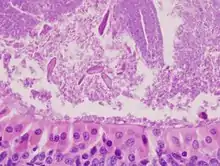

Histopathology of Warthin tumor in the parotid gland. H&E stain. (Fig 1)

Histopathology of Warthin tumor in the parotid gland. Another view of Fig 1

Histopathology of Warthin tumor in the parotid gland. Higher magnification of a Fig 1

The appearance of this tumor under the microscope is unique. There are cystic spaces surrounded by two uniform rows of epithelial cells with centrally placed pyknotic nuclei. The cystic spaces have epithelium referred to as papillary infoldings that protrude into them. Additionally, the epithelium has lymphoid stroma with germinal center formation.